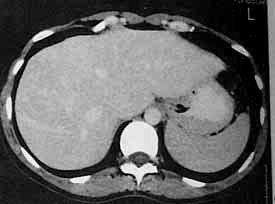

患者女,39岁,无相关症状.平扫显示肝内两个孤立的低密度灶.